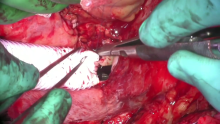

Through a fourth sternotomy, the innominate artery, both the superior vena cava, and the right common femoral vein were cannulated for cardiopulmonary bypass (CPB). After cardioplegic arrest, an atriotomy was performed, and the Fontan conduit was resected. The pulmonary confluence and the inferior vena cava were disconnected from the atrium, and both atrial ends were oversewn. A 20 mm polytetrafluoroethylene graft was then used for the extracardiac Fontan reconstruction. The patient was subsequently weaned off CPB without difficulty and extubated in the operating room.He was discharged seven days later.